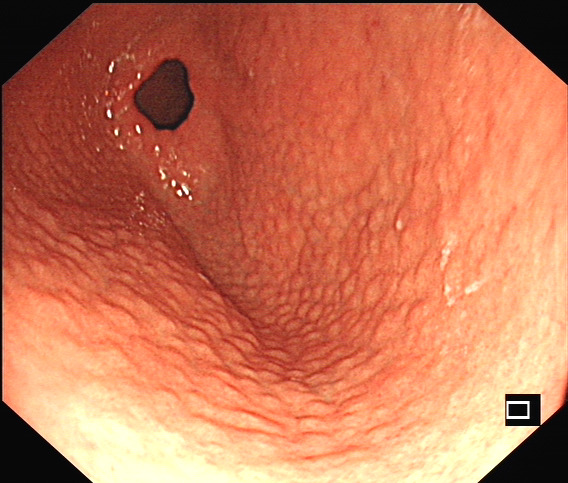

幽门螺旋杆菌感染临床上颇为常见,本次查看体检结果,发现一个“珍珠胃”的,其实就是胃窦结节样改变,这个是幽门螺旋杆菌感染内镜下最典型的一个表现了,其他的还有粘膜发红充血、息肉等,相对来说缺乏一些特异性。

幽门螺旋杆菌感染相关胃炎胃镜下表现